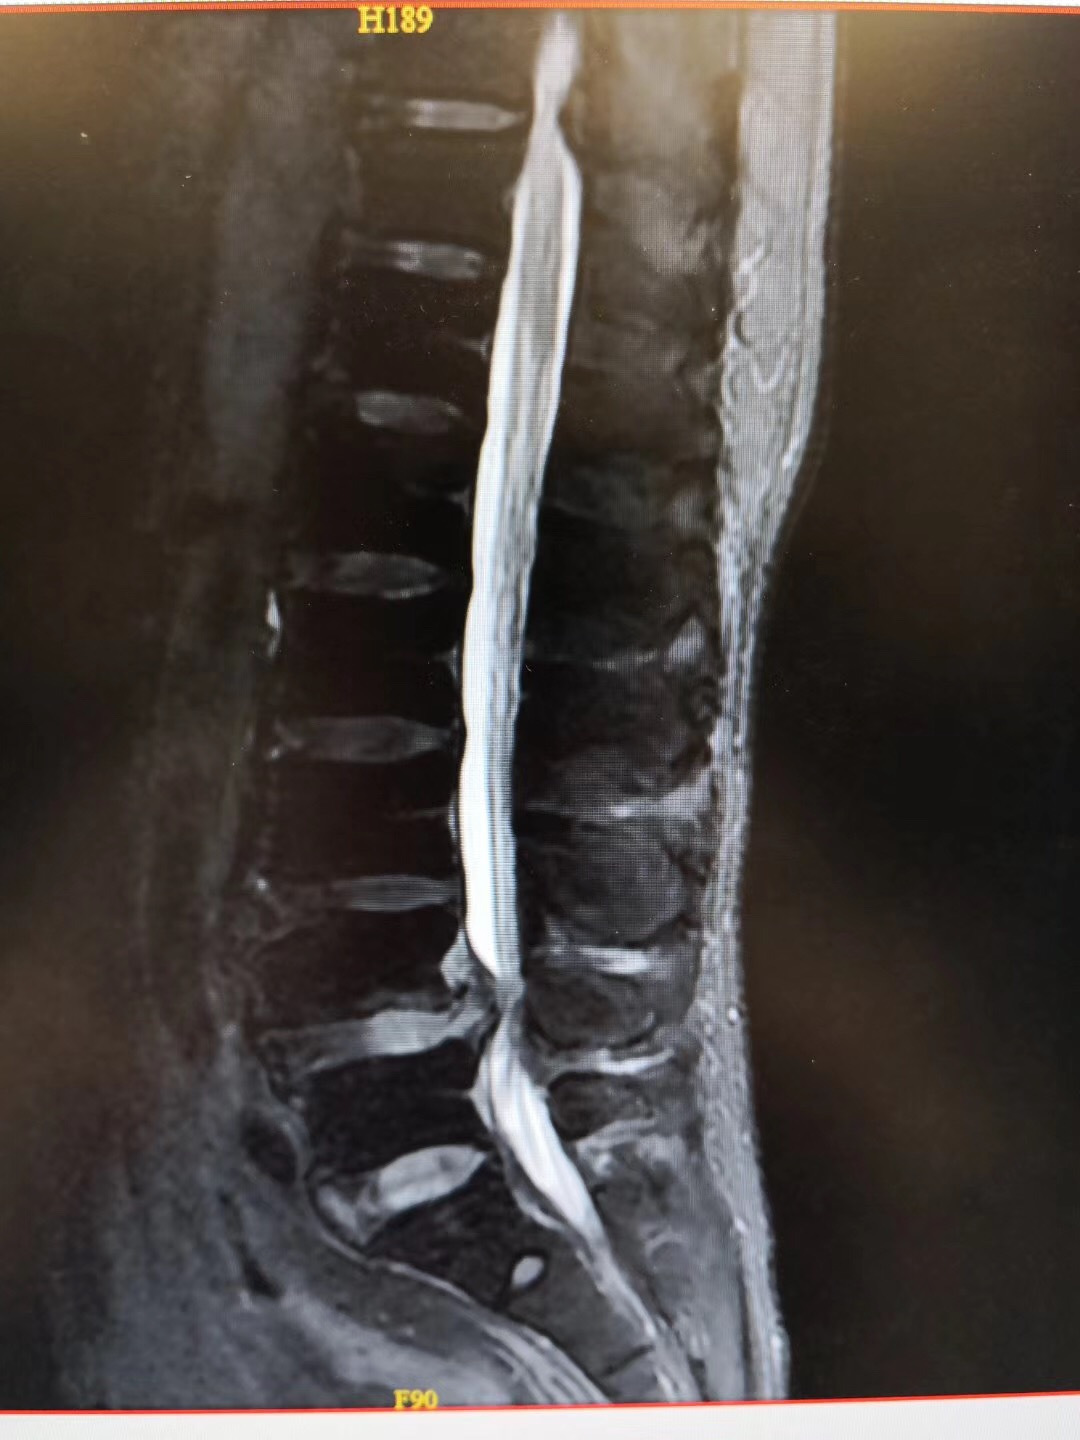

患者:65岁男性,广东湛江籍。

症状:双下肢麻痛伴间歇性跛行1年,行走100米即出现双下肢麻痛,严重影响生活。

诊断:腰椎间盘突出伴椎管狭窄症(L4/5节段),腰椎不稳定(L4/5节段),予施行“后路腰椎管减压固定融合术”治疗。

术后:术后第二天患者即可腰围保护下床行走活动,双下肢麻痛基本缓解,效果良好!